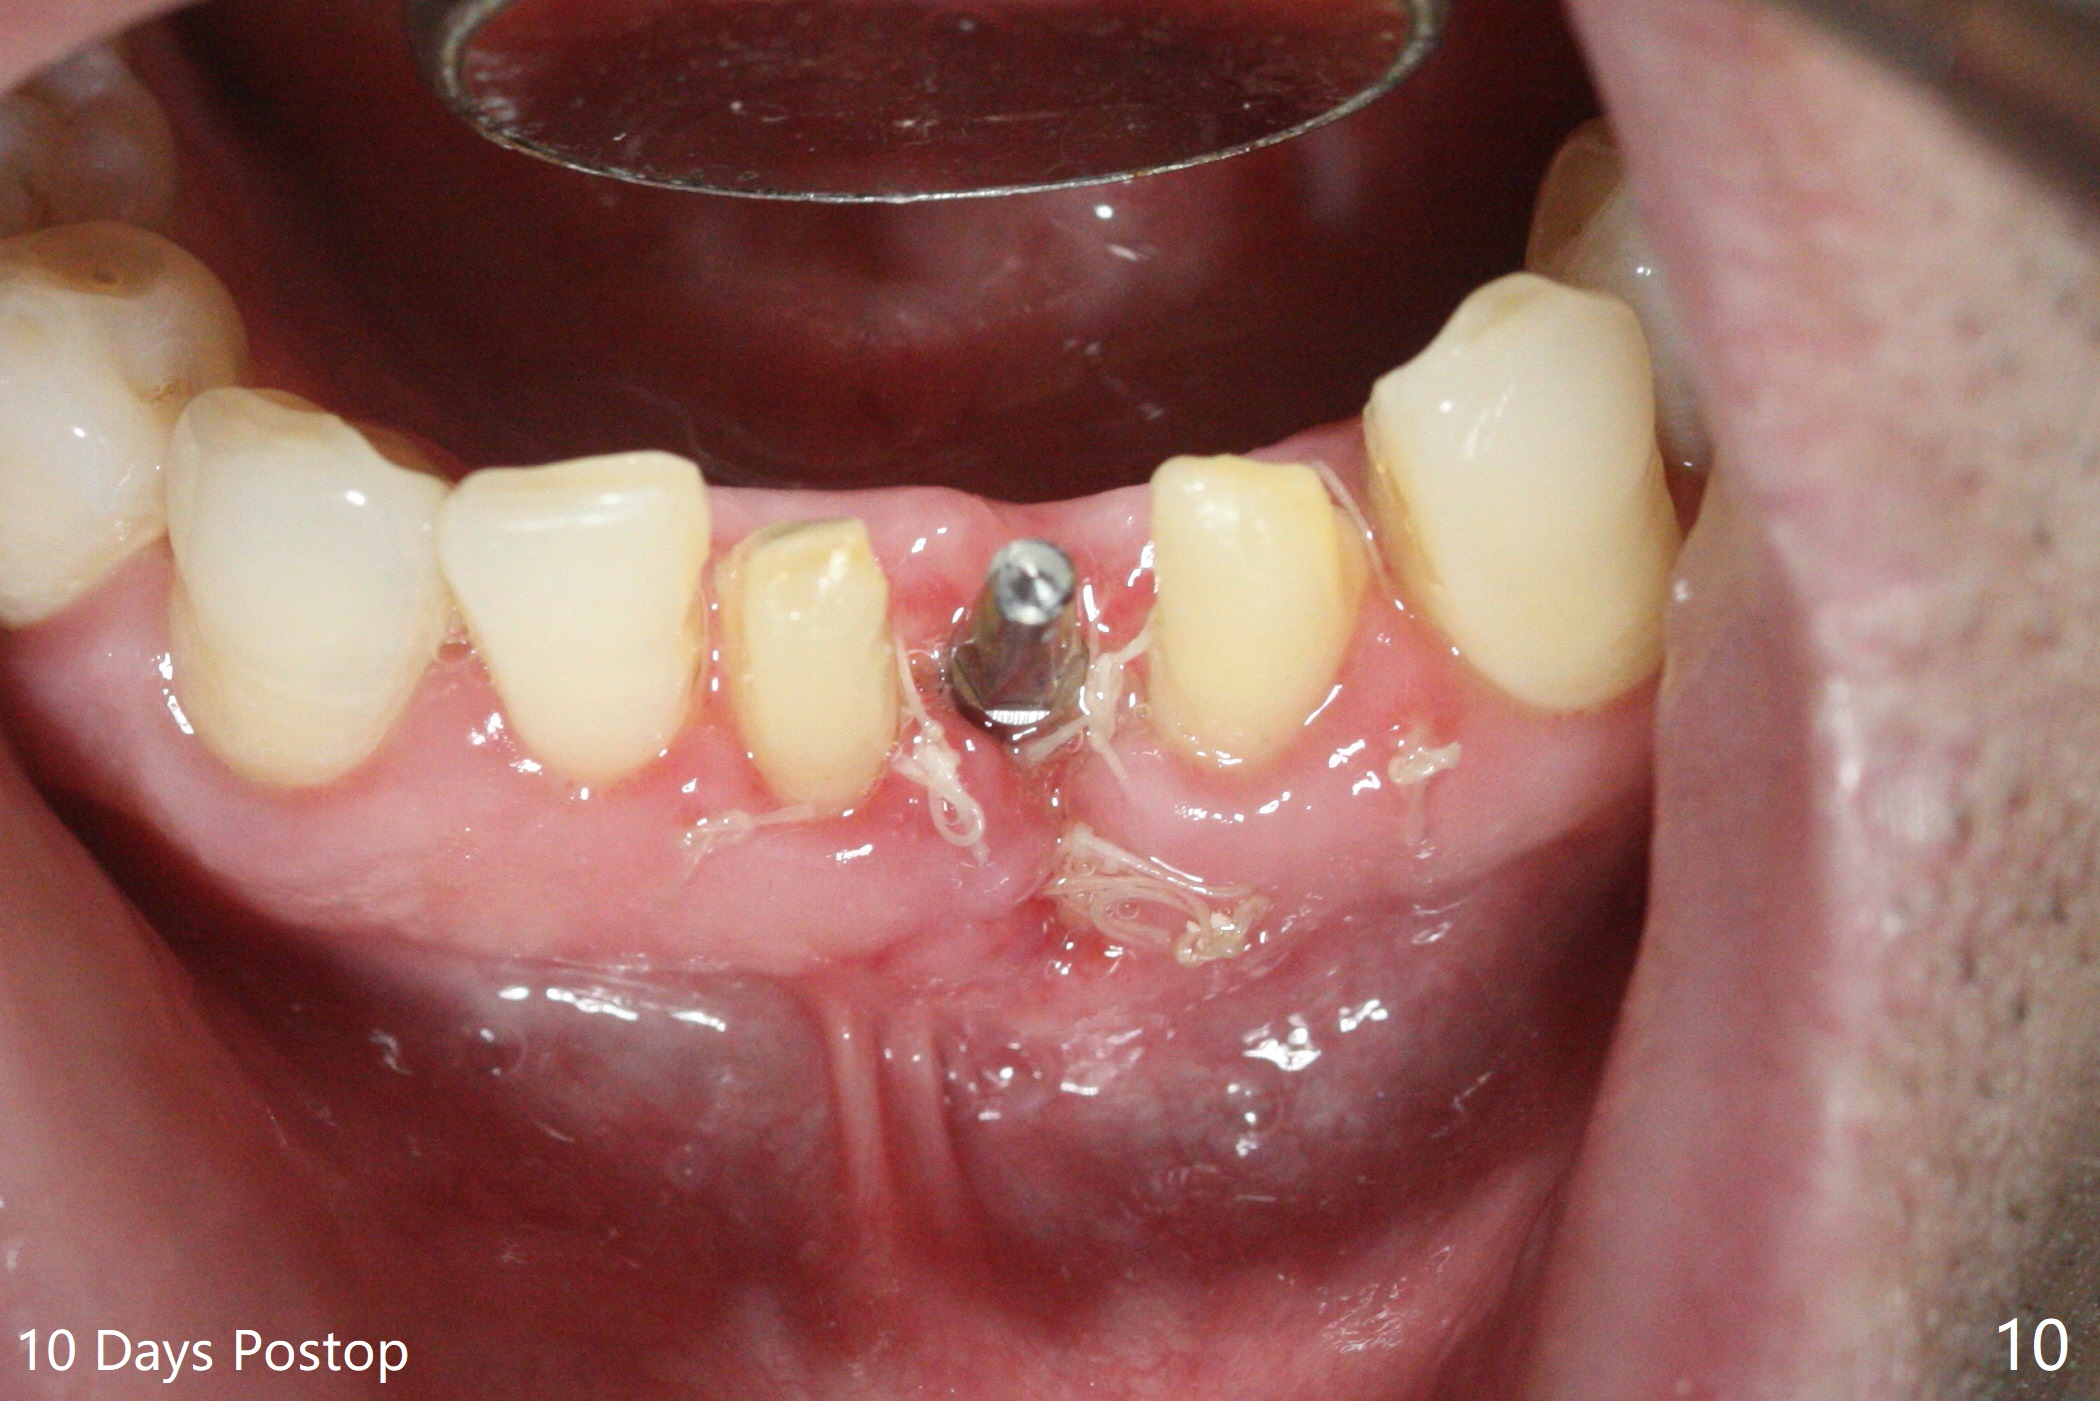

经过深洗以及改善口腔卫生,术前下前牙区牙龈基本没有红肿,但是缺牙处牙龈凹陷(图一,二:箭头),这个现象代表什么?如何影响手术进路?其实后者部分是因为牙龈与下面骨质(骨嵴)粘连(图三:*)产生的,分离粘骨膜瓣时不小心撕裂颊侧牙龈(图三(骨膜分离器下面:#),造成后来缝合困难,需要多用一个胎盘膜)。如果术前仔细分析CT 3D图像(图四,五)可以发现严重颊侧骨壁凹陷(图三:^)以及骨嵴(图四:*),事先抽血制备PRF膜和粘性骨粉,植骨效果好些(图六)。术中发现缺损,再抽血会拖延手术。最后将就用血调袢骨粉,使用胶原膜和胎盘膜覆盖(图七,八)。颊侧裂口术后十天愈合了(图九,十)。术后一个月颊侧牙龈凹陷,牙桥边缘(图十一:箭头)粗糙,临时牙桥取出,调整边缘,有利于局部卫生(图十二)。术后两个月桥边缘光滑(图十三:箭头),局部卫生和牙龈凹陷有所改善。病人将一个半月后回来取模。Return to Protect Graft 前磨牙即种 101 Xin Wei, DDS, PhD, MS 1st edition 04/30/2021, last revision 07/03/2021